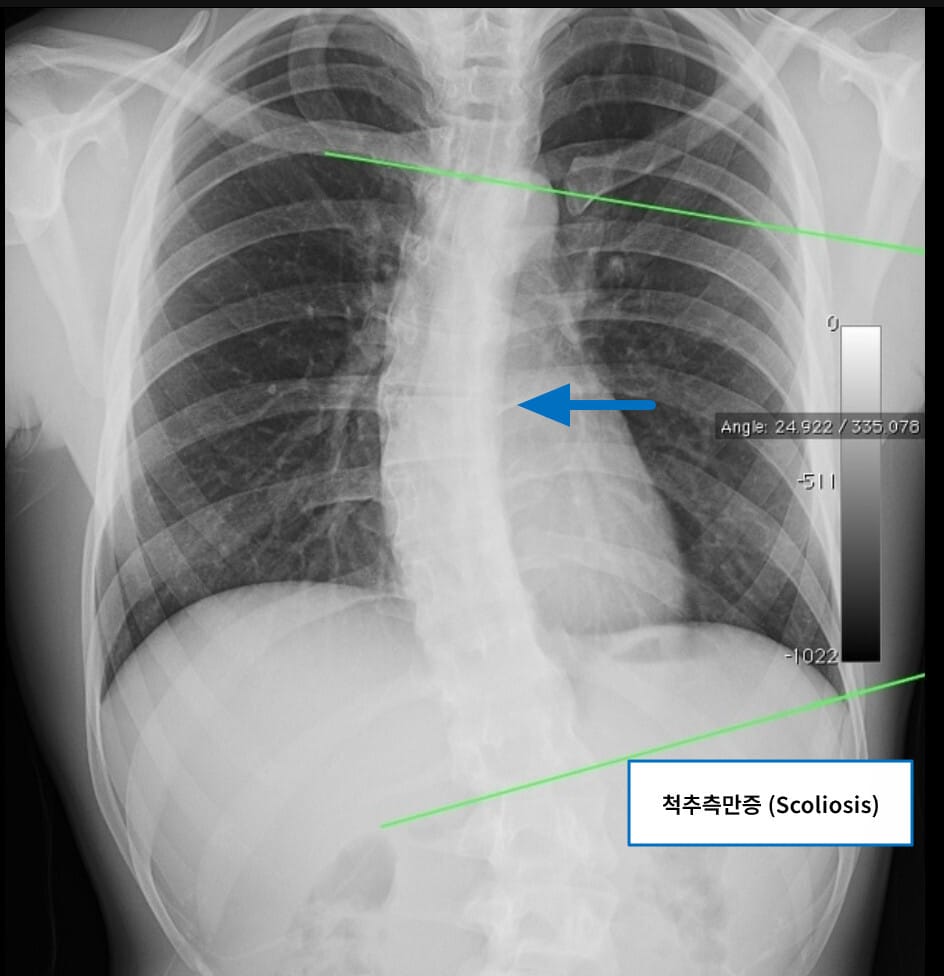

Scoliosis (척추 측만증)

척추 측만증은 척추가 정면에서 볼 때 옆으로 휘어진 변형으로, S자형 또는 C자형으로 변형될 수 있습니다.

| 🟧 척추가 좌우로 휘는 구조적 변형 |

| 측정 기준인 Cobb angle이 10도 이상일 때 진단하며, 청소년기 특히 여성에서 흔합니다. |

| 🟧 비대칭적인 어깨 및 골반 |

| 거울을 보면 한쪽 어깨가 높거나, 골반이 틀어져 있는 경우가 많습니다. |